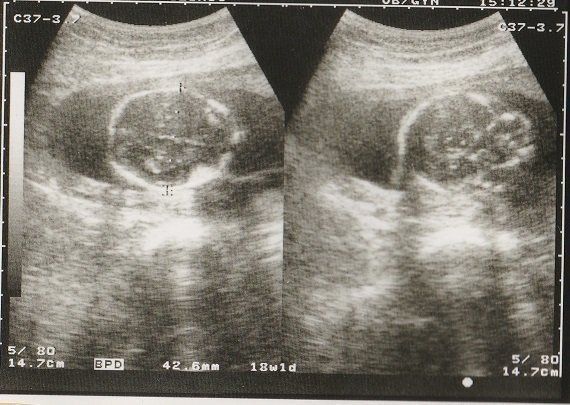

妊娠16週目のエコー写真 安定期に突入

「ここが顔だなあ」と、わかるようになってきました。妊娠中期で安定期になりましたが、おなかの赤ちゃんのためにも油断は禁物と考えていた時期です。

妊娠18週目のエコー写真 画像におさまらないほどに成長する

赤ちゃんがどんどん大きくなり、1枚の超音波画像ではおさまりきらなくなりました。画像を2枚くっつけて赤ちゃんの大きさを測っています。

BPD(児頭大横径=頭の直径)を測って、胎児の発育を調べるようです。ここまで、母子ともに特に異常も無く過ごせました。